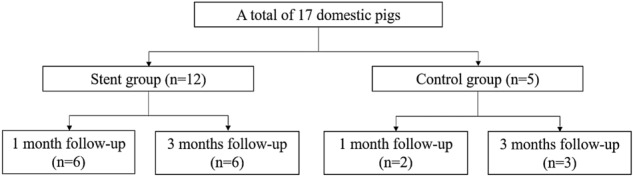

A total of 17 domestic male pigs (age, 3 months; weight, 26–30 kg) were divided into a stent group with 1-month follow-up (n = 6), stent group with a 3-month follow-up (n = 6), control group with a 1-month follow-up (n = 2), and control group with a 3-month follow-up (n = 3) (Fig. 2). 3 of the 6 stents used in stent group with a 3-month follow-up were prototype. All other stents were final version.